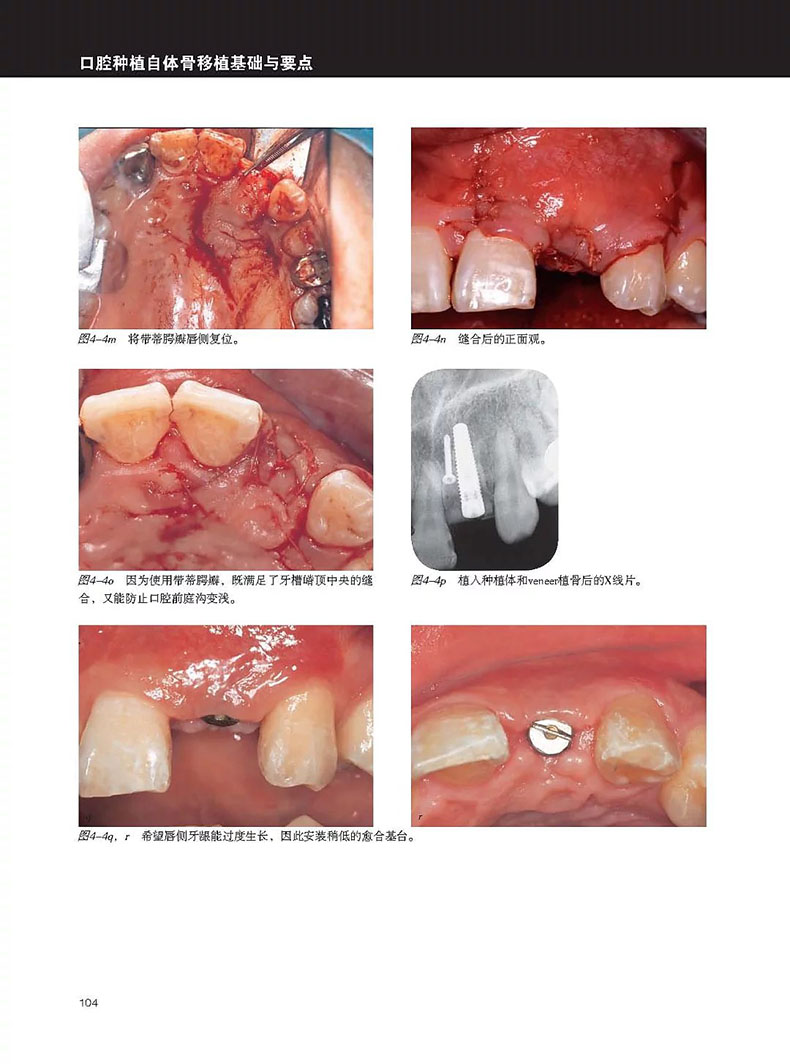

單顆上前牙缺失